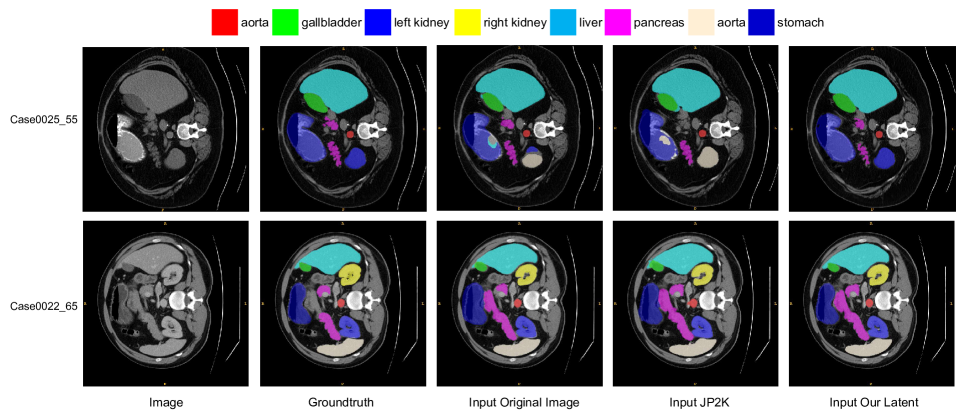

Refer to caption

Figure 9: Qualitative comparison of different segmentation approaches by visualization. From left to right: (1)original image (2)ground truth, (3)take the original image as input, (4)take the compressed image by JP2K as input, (5)take the latent decoding by our framework as input. In detail, the bits per pixel (BPP) of (4)JP2K is 0.266, and the BPP of (5)Our Latent is 0.2735.

In addition to human vision tasks, we further explore the effectiveness of using decoded intermediate features to perform machine vision tasks. We design two models Our Latents and Our Image. For Our Latents model, we feed the partially decoded intermediate features Mxsubscript𝑀𝑥M_{x} into the medical image segmentation networks shown in Fig. 2. For Our Image model, we first perform image reconstruction and then input the recovered pixel-level frames into the segmentation network. As for comparison, following[31], we perform additional experiments using the traditional image compression algorithm JP2K. We first apply the JP2K algorithm to compress the CHAOS, ACDC, and Synapse datasets at compression rates of 20, 25, 40, 60, 80. Subsequently, we feed the compressed images into the segmentation network to obtain the predicted masks. For Our Latents method, we adjust the number of input channels in the TransUnet network to fit the latent decoding feature. In Our Image and JP2K experiments, we modify the input channel number to 111.

We present the detailed experimental results in Fig. 8. The red lines represent inputting the original images without compression into the TransUnet network, which means the bits per pixel are equal to the original data, i.e. 16. To compare with it, we perform experiments of three compression methods in different ratios and plot the DICE-BPP and HD95-BPP curves.